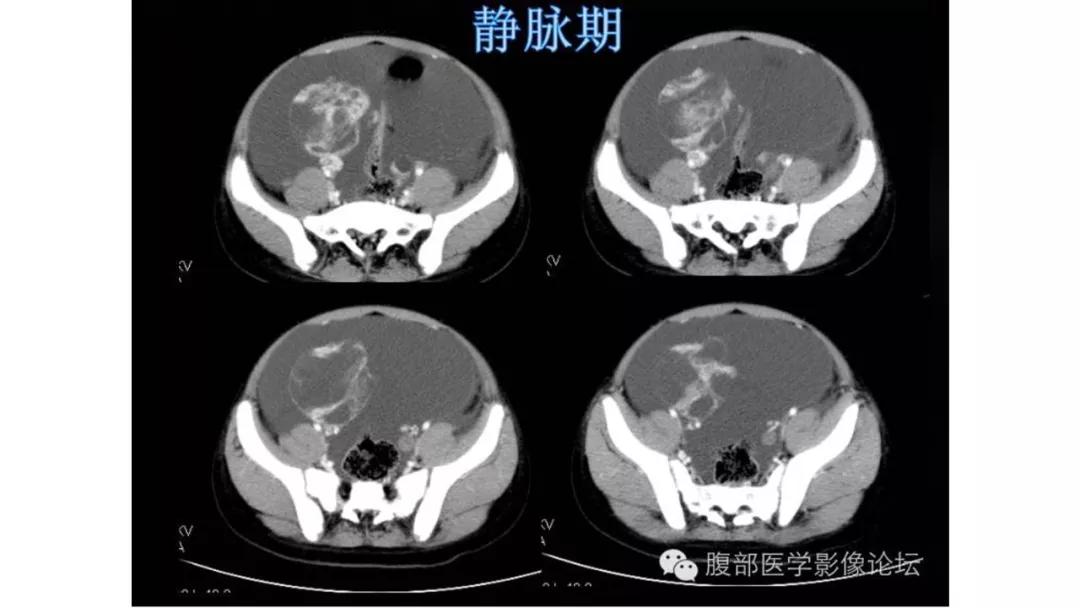

病理:浆液性囊腺癌